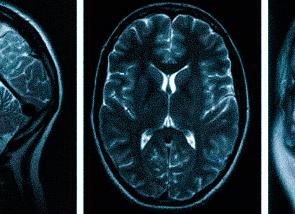

Исследование МРТ является диагностическим способом выявления патологий внутренних органов, который основывается на воздействии магнитного поля. Процедура делает возможным детальный обзор всех слоев мозга с последующим отображением картинки в трехмерном формате на компьютерный экран, что способствует определению развития болезни, а также подобрать подходящую терапевтическую методику. При наличии головных болей МРТ делать обязательно.

Процедура делает возможным детальный обзор всех слоев мозга.